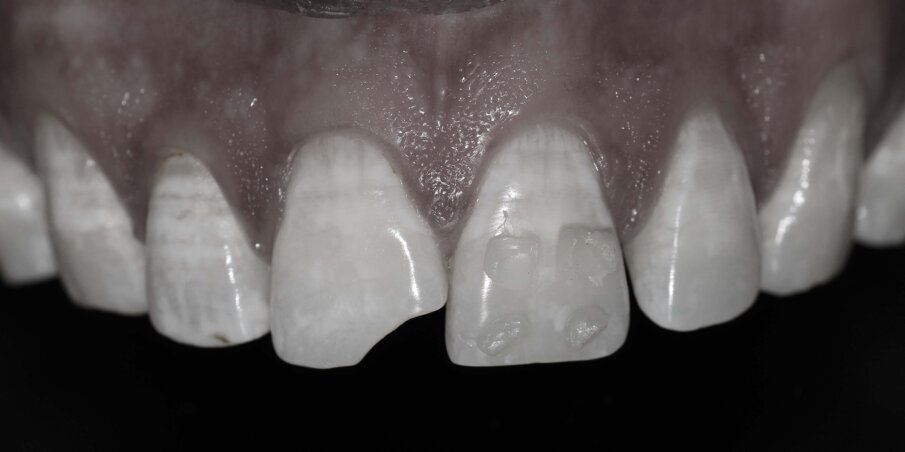

It was decided to restore the tooth with Direct Composite Resin. Preoperative photographic records were taken. Small buttons of different shades (dentin, body and enamel shades of A1 and A2) of composite resin were placed on the adjacent teeth and photographs were taken with different settings to ascertain the correct value and chroma of the material to be used (button technique).

Fig 3: Composite button technique for selecting the Shade (Hue)

Fig 4: Monochromatic picture for selecting the Value

Fig 5: Deep View to select the correct Chroma